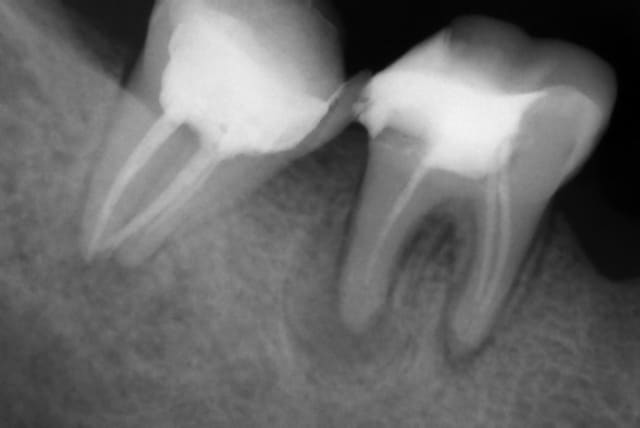

Je récupère une patiente avec un nécro sur la 47.

J'effectue le TR: sur la DP je suis à l'apex, la MV je suis à 4mm de l'apex mais je n'arrive pas à progresser et sur la ML je ne vois pas l'apex à la radio mais je dépasse clairement de 3mm.

La patiente a des douleurs au toucher dela table alvéolaire interne, à la pression et des démangeaisons!

J'ai désobturé le canal ML et j'y ai mis de l'hydroxyde de calcium.